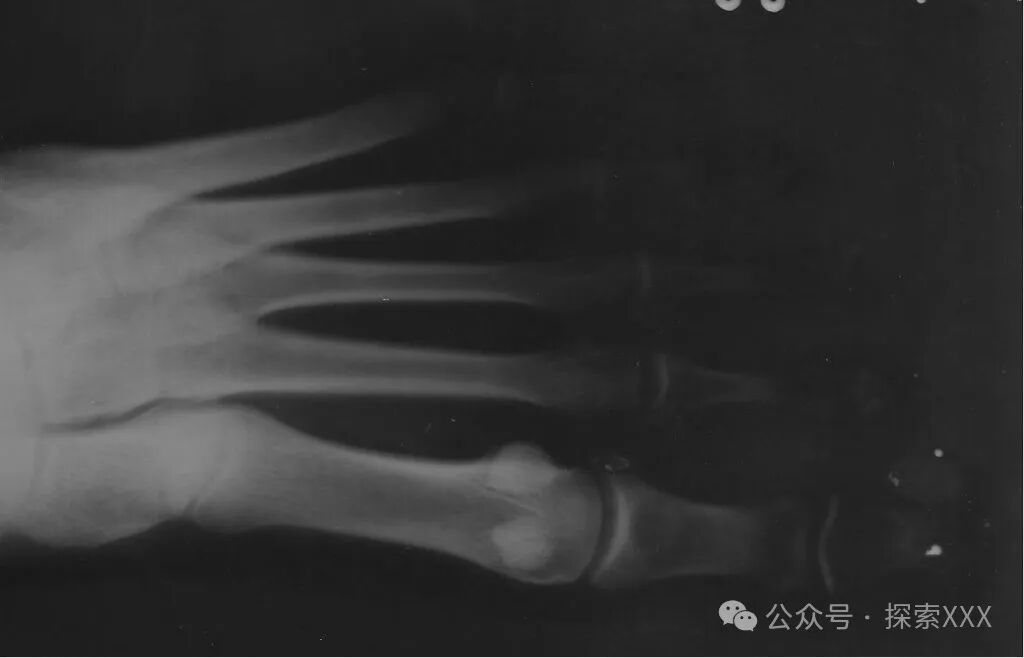

在催眠结束一段时候后,UFO调查员马里奥·诺盖拉·兰格尔问贝特,是否可以给她的右脚大脚趾拍个X光片。因为在绑架过程中,她感到右脚大脚趾被刺痛,怀疑被植入了异物。

贝特脚趾的X光片

贝特接受了这个请求,随后在两个不同的位置进行了检查。令贝特惊讶的是,X光图像显示,她的拇趾的柔软部分有两个金属体。这些物体非常小,并且是金属的。贝特还曾联系了罗杰·莱尔博士,作为外星植入方面的专家,他检查了贝特的脚趾,并提出可以移除这些物体。

但贝特不想移除它们。按照贝特的说法,她从来就没有感觉到要取出它们的冲动。

我不知道为什么它会出现在我的身体里,但它并没有伤害我或造成任何健康问题。我想我一定参与了绑架者的一些研究或经历,因为它们从小就陪伴着我,虽然我不知道它们选择我的标准是什么,它们这样做是否有意义......它们的行为都表明它们是认真、投入的科学家。